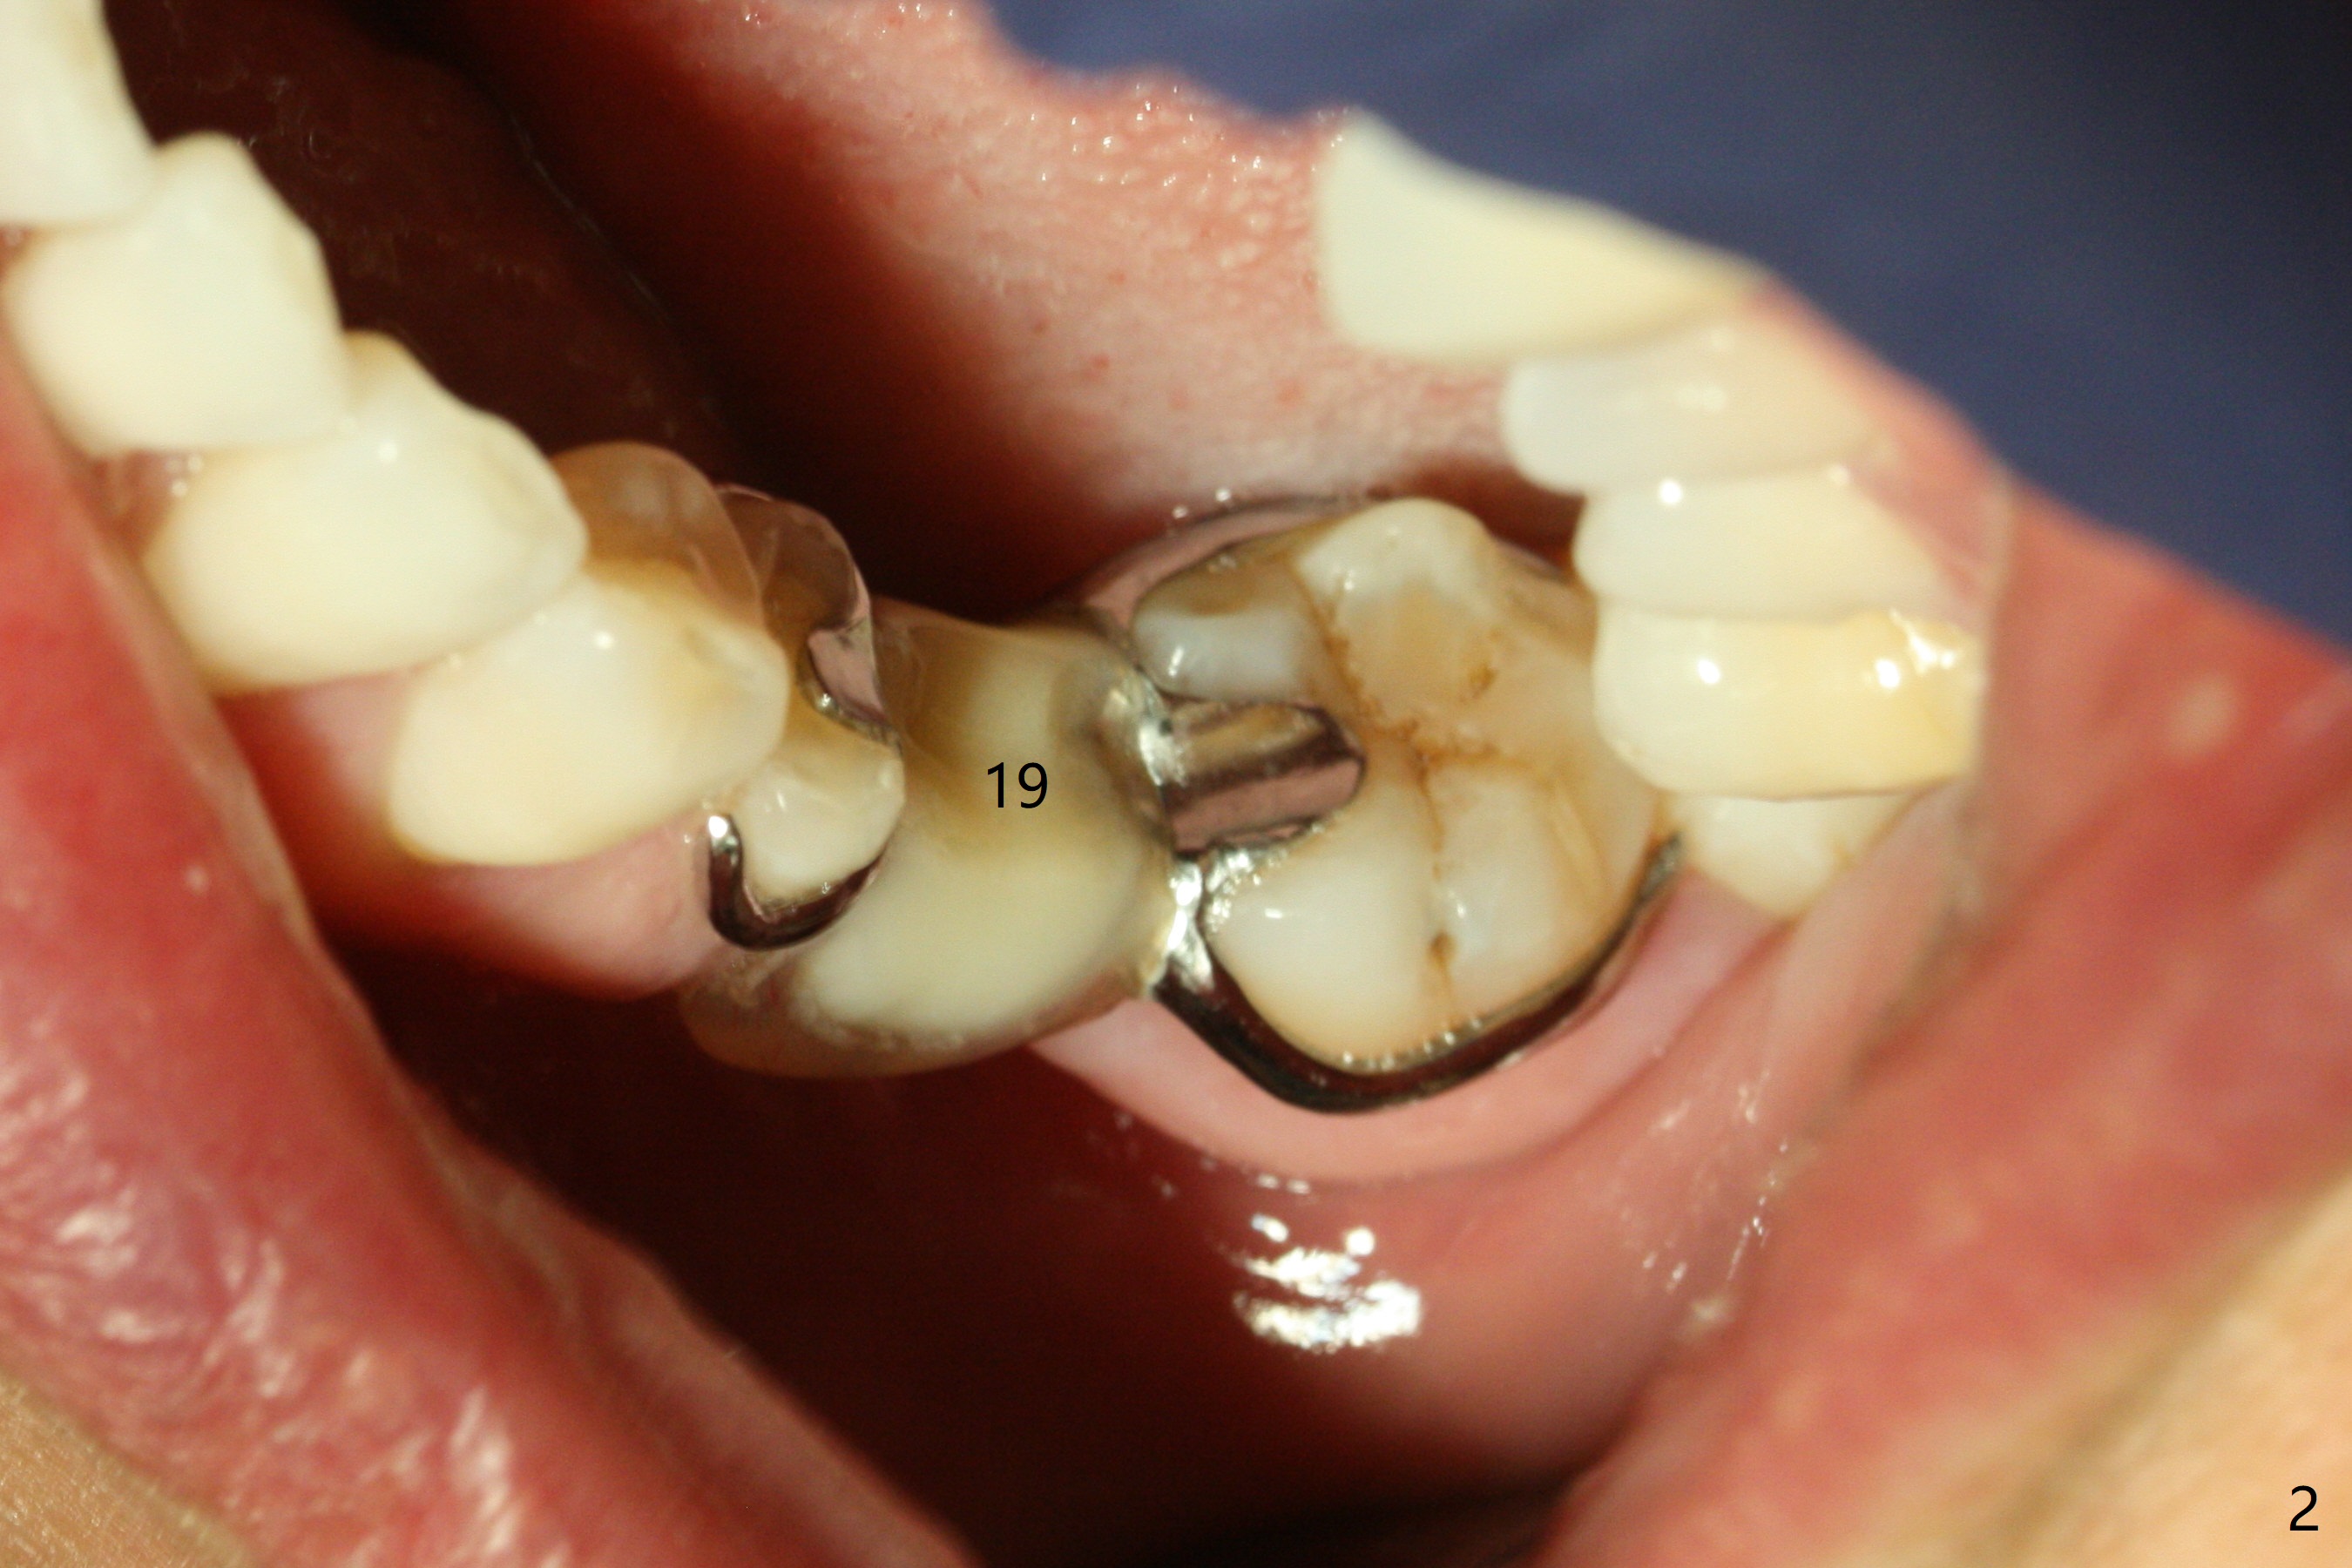

Fourteen days prior to implantation at #19 to replace a flipper (Fig.2), two minimplants are placed to intrude the supraerupted opposing tooth (#14, Fig.1). After use of minimal amount of local anesthetic (to keep proprioceptive in case root surface violation), the miniimplants are inserted ~ half of the length initially (Fig.3,4). The mesiobuccal (MB) one seems to be better positioned than the distopalatal (DP) one. When the implants are completely seated (Fig.5,6), three of PAs are taken, which suggests contact of the MB implant to the MB root of the tooth #14 (Fig.7 arrow). Immediately postop CT confirms approximation of MB and DP implants to the MB and P roots, respectively (Fig.8,9). The trajectory of these implants remain unchanged. Twelve days postop, the patient returns, uncomfortable with the palatal implant. After deep placement to bury the cuff (Fig.6) without local anesthesia (bone having no innervation), the patient feels better.